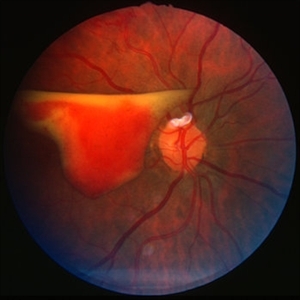

Preretinal hemorrhage - BRVO

Altered preretinal haemorrhage from neovascularisation due to right branch retinal vein obstruction (BRVO).

Condition/keywords: branch retinal vein occlusion (BRVO), preretinal hemorrhage